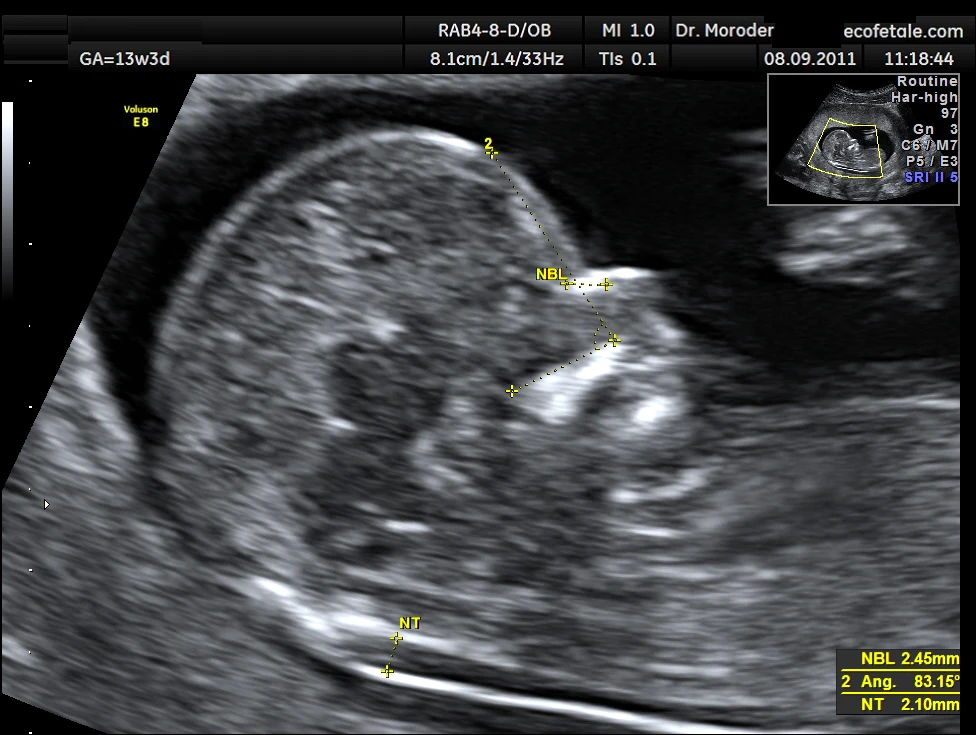

Siêu âm độ mờ da gáy đóng một vai trò không thể thiếu trong quá trình sàng lọc hội chứng Down và các dị tật bẩm sinh khác ở thai nhi. Việc này không chỉ giúp cho việc phát hiện sớm những nguy cơ tiềm ẩn mà còn tạo điều kiện cho các bậc phụ huynh chuẩn bị tâm lý và kế hoạch chăm sóc sức khỏe tốt nhất cho đứa trẻ. Khi thực hiện siêu âm, các bác sĩ sẽ đo lượng dịch tích tụ dưới da ở vùng sau gáy của thai nhi. Độ mờ da gáy càng cao, nguy cơ mắc các bất thường về nhiễm sắc thể càng lớn. Quá trình này diễn ra trong giai đoạn từ tuần 11 đến tuần 13 tuần 6 ngày, đây là thời kỳ "vàng" để thu thập dữ liệu chính xác nhất.

- Đo kiểm tra: Đo độ mờ da gáy thực hiện qua nhiều lần để đảm bảo chính xác. Bác sĩ sẽ đo độ dày lớp dịch ở vùng gáy và sử dụng kết quả trung bình của các lần đo để làm dữ liệu cuối cùng. Đây là thời điểm để phát hiện các bất thường có thể xảy ra, như độ mờ Độ mờ da gáy trên 3 mm.

Kết quả siêu âm độ mờ da gáy thường được biểu thị bằng độ dày (đo bằng mm) của dịch tích tụ ở vùng da gáy. Kết quả này đóng vai trò then chốt trong việc sàng lọc sớm nguy cơ mắc các dị tật bẩm sinh hay các rối loạn nhiễm sắc thể ở thai nhi, đặc biệt là hội chứng Down. Nếu so sánh với những bức ảnh siêu âm, độ mờ da gáy có thể được ví như một bức tranh minh họa về tình hình sức khỏe tổng thể của thai nhi.

Kết quả bình thường thường có độ mờ da gáy dưới 3 mm, cho thấy nguy cơ thấp về của các dị tật. Tuy nhiên, nếu độ mờ da gáy từ 3 mm trở lên, đây có thể là dấu hiệu cảnh báo cần thận trọng, kích thích sự tiếp diễn của một loạt các xét nghiệm khác nhằm xác định cụ thể nguyên nhân. Trong các trường hợp này, bác sĩ có thể chỉ định Double Test hay chọc ối để có thêm thông tin.

Mức độ mờ da gáy là một chỉ số thiết yếu trong siêu âm thai nghén, cho phép bác sĩ đưa ra đánh giá về tình trạng sức khỏe của thai nhi. Kết quả này được tính bằng độ dày của dịch tích tụ dưới da ở vùng gáy của thai, tính bằng mm.

Mức độ mờ da gáy bình thường thường là dưới 2.8 mm, cho thấy một nguy cơ thấp về các dị tật nhiễm sắc thể. Đối với các thai nhi có độ mờ da gáy từ 2.8 mm đến 3 mm, bác sĩ thường sẽ cân nhắc kết hợp với các dữ liệu sàng lọc khác như Double test hoặc Triple test để xác định nguy cơ. Những trường hợp có mức độ mờ da gáy trên 3 mm sẽ được coi là rủi ro cao, cần thực hiện thêm các xét nghiệm xâm lấn để có kết quả chính xác hơn.